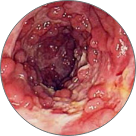

Tromboza proširenih vena anusa sa lokalnom nekrozom tkiva

Venska zapušenja s patološki izmenjenim varikoznim venama

Submukozno krvarenje koje dovodi do nekroze tkiva i anemije

Rak rektuma

Hemoroidi su ozbiljna bolest koja pogađa jednu od dve osobe širom sveta. Bol, peckanje, svrbež i krvarenje početni su simptomi koje ni u kojem slučaju ne treba zanemariti. Kao rezultat ulaska krvi u venski pleksus rektuma, dolazi do upalnog stanja, nakon čega se na rektalnom tkivu stvaraju krvavi čvorovi.

Najsavremeniji preparat brzo, lako i 100% sigurno uklanja krvareće čvorove. Aktivni sastojci sadržani u formuli popravljaju oštećenja tkiva i obnavljaju vaskularne pleksuse od prve primene proizvoda. Opuštanje ovih struktura omogućuje lakše pražnjenje, eliminirajući na taj način zatvor i stvaranje hemoroida.